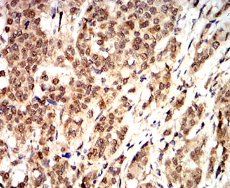

CCND1 Mouse Monoclonal antibody[3B6G9]

Immunogen :   Purified recombinant fragment of human CCND1 (AA: 167-295) expressed in E. Coli.

IHC    1/200 - 1/1000